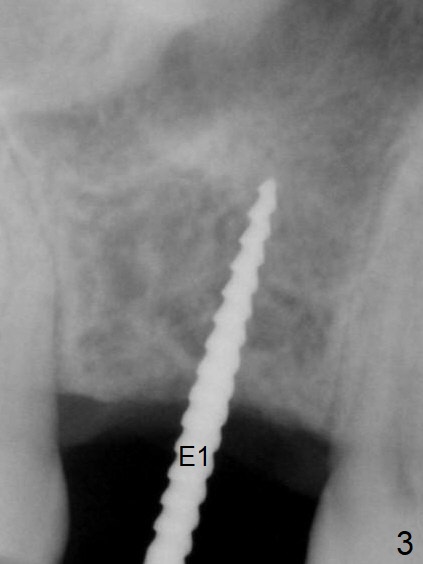

A 54-year-old man has lost the tooth #3 for 6 months with complicated sinus floor morphology (Fig.1 red dashed line (one of 2 outlines), bone height ~ 7 mm). Initial osteotomy depth is ~ 6 mm (Fig.2,3 with 1.2 mm initial drill and DIO Bone Expander 1 (E1 with diameter 1.0/1.6 mm). Following change in the trajectory, E2 (1.3/2.3 mm) is used for ~ 8 mm (Fig.4). After application of E4 (2.4/3.7 mm, Fig.5) and E5 (3.0/4.4 mm) for ~ 12 mm, the sinus membrane is found to have perforated. With placement of collagen membrane and cortical allograft (Fig.6 *), a 5x8.5 mm Hiossen implant is placed with >50 Ncm.